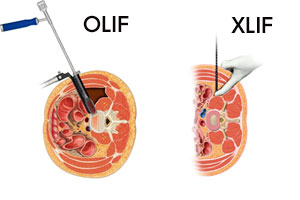

手術方法も急速に進歩しており、体にやさしい最小侵襲手術(MIS : Minimally Invasive Surgery)により、社会復帰が早くなり、ご高齢の患者様も受けられるようになってきました。腰部椎間板ヘルニアや腰部脊柱管狭窄症、頚椎症性神経根症に対する内視鏡視下手術、骨粗鬆症性椎体圧迫骨折に対する経皮的椎体形成術(セメント注入術)、腰椎変性疾患に対する小切開での固定術をはじめ、脊柱変形に対しての側方進入前方固定術(OLIFやXLIF)は安全に行えば従来法に比べて手術時間、出血量を大幅に減らすことが可能です。

脊柱変形(側弯、後弯症)

脊柱側弯症や腰椎後弯症(腰曲がり)は姿勢異常だけでなく、頑固な腰痛、下肢の痛み、しびれ、さらには食欲の低下、胃腸障害などを引き起こすこともあります。このような場合には脊柱変形矯正術を行います。以前はご高齢の患者様にとってはかなり負担の大きな手術でしたが、側方進入腰椎前方固定術(OLIFやXLIF)の導入により、安全に行えば手術時間や出血量を大幅に減らすことが出来るようになりました。

側方進入前方固定術

側方進入前方固定術とは、体の側方から手術を行う方法です。従来の前方固定術をさらに低侵襲にした方法です。

適応疾患

脊柱変形、腰部脊柱管狭窄症、腰椎すべり症、脊椎外傷、腰椎多数回手術後症状遺残等

側方進入前方固定術のメリット

低侵襲の手術なのでお体への負担が少なく、また従来よりも大型の固定具が設置できるため、術後の安定感が高まり、骨との結合が早まります。

入院期間

2-3週間程度、脊柱変形の場合は1か月程度